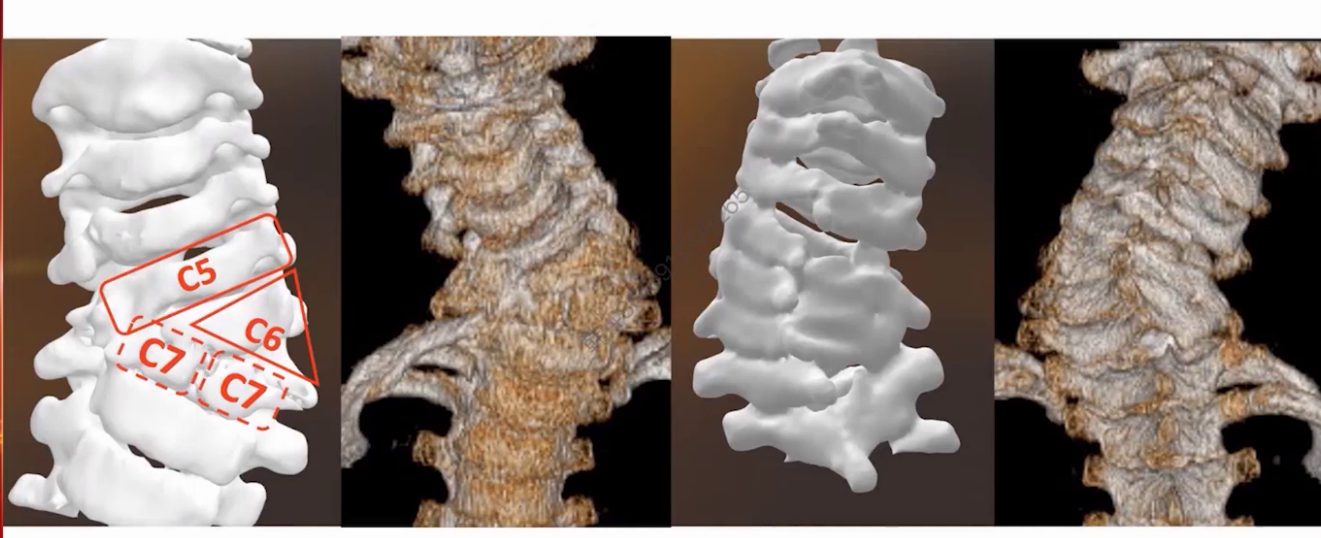

CT显示C5-C7椎体分界不清,伴对侧骨桥形成。三维重建更清晰展示局部畸形结构。